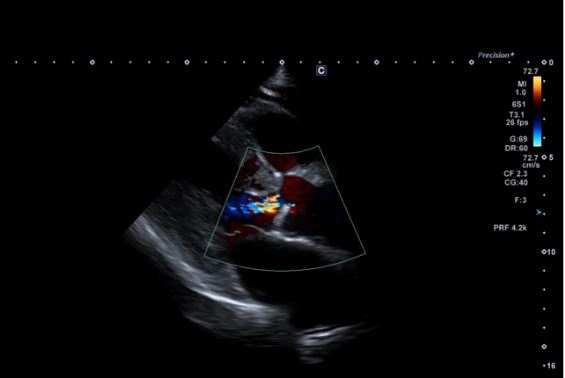

Вигляд 2D LV PLAX. Кольоровий допплер з високою чутливістю може забезпечити чітку візуалізацію аортальної регургітації.